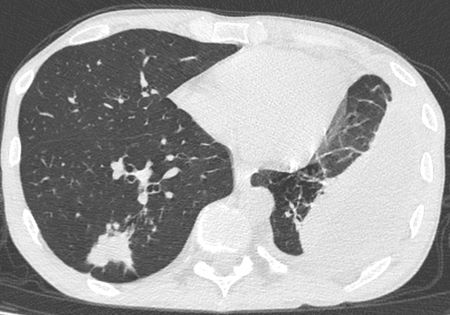

При исследовании в верхушке левого лёгкого было выявлено, субплеврально, полостное образование с толстыми стенками (толщиной до 3,5 мм) с нечёткими и неровными контурами, с прилежанием к костальной плевре на широком основании, размерами 26х22 мм. Вокруг данного образования определялся участок консолидации с прослеживающимися, суженными, деформированными просветами бронхов. Каудальнее образования и участка консолидации определялись хаотично расположенные очаги размером до 7 мм. В S1-2 левого лёгкого субплеврально определялось округлое образование с чёткими, неровными контурами с прилежанием к костальной плевре, размером до 11 мм. В левой плевральной полости жидкостное содержимое с максимальной сепарацией листков плевры до 54 мм, на этом фоне листки плевры были уплотнены, утолщены до 7 мм. На фоне жидкостного содержимого в плевральной полости, в паренхиме левого лёгкого отмечались множественные линейные фиброзные тяжи. В S6, S9 правого лёгкого, перибронховаскулярно, определялись множественные очаги по типу «дерева в почках» (размером до 6 мм), сливающиеся между собой с формированием участка консолидации размером до 27 мм. Кроме того, в правом лёгком определялись множественные мелкие центрилобулярные и субплеварльные очаги уплотнения размером до 4 мм.

Отмечался перелом переднего отрезка 5-го ребра справа с формированием диастаза между отломками до10 мм. В окружающих мягких тканях мелкие костные структуры размером до 2 мм.Заключение

С учетом анамнеза и данных МСКТ-исследования было вынесено заключение КТ-картины полостного образования в верхушке левого лёгкого, с наличием участка консолидации, очагов отсева в верхней доле левого лёгкого, субплеврального образования в верхней доле левого лёгкого, левостороннего плеврального выпота, с признаками утолщения листков плевры, фиброзных изменений левого лёгкого, очагов по типу «дерева в почках» с формированием участка консолидации в нижней доле правого лёгкого (данные изменения, вероятно, соответствуют проявлениям вторичного туберкулёза, дифференцированного с периферическим образованием с признаками вторичных изменений. Перелом переднего отрезка 5-го ребра справа.